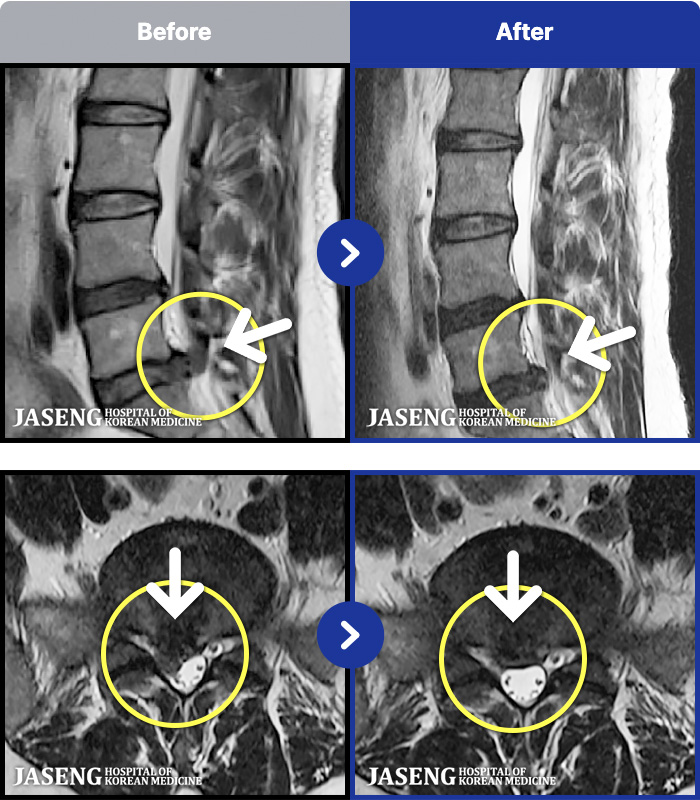

[뱸] 19.11.28~25.05.06